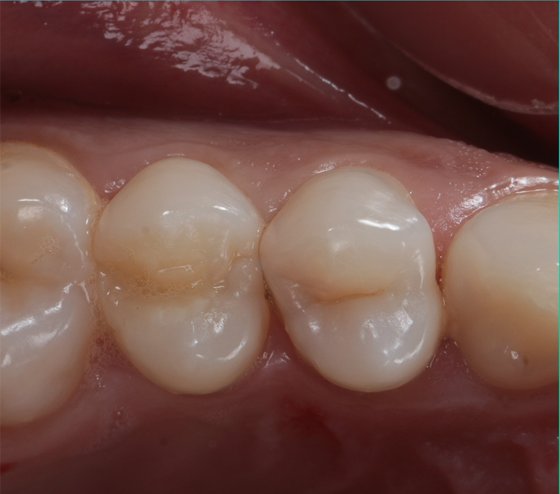

Final result.

Final result